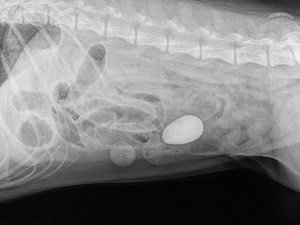

Большинство клинических проявлений заболеваний ЖКТ не имеют четкой картины. Их трудно отнести к какому-то конкретному органу. Поэтому для визуализации патологического процесса в брюшной области проводится УЗИ и рентгенография.

Рентген предпочтительно проводить с использованием контраста (соли бария). Он позволяет получить четкую визуализацию органов, выявить механическую непроходимость кишечника. С помощью нескольких снимков, сделанных через определенные промежутки времени, можно отследить продвижение контрастного вещества по ЖКТ. Если оно не двигается, а зафиксировалось в одном месте, речь идет о непроходимости.